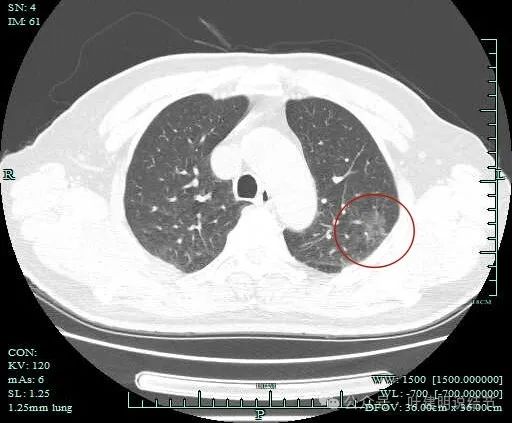

密度不纯,有少许偏实性成分出现,边缘毛刺明显,感觉病灶有一定收缩力。

混合密度,轻微胸膜牵拉,边缘细毛刺,灶内质不均,表面有浅分叶。

灶内有血管穿行或新生血管的样子,边缘细毛刺明显。